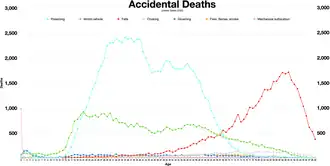

Asphyxia or asphyxiation is a condition of deficient supply of oxygen to the body which arises from abnormal breathing.[3][4] Asphyxia causes generalized hypoxia, which affects all the tissues and organs, some more rapidly than others. There are many circumstances that can induce asphyxia, all of which are characterized by the inability of a person to acquire sufficient oxygen through breathing for an extended period of time. Asphyxia can cause coma or death. In 2015, about 9.8 million cases of unintentional suffocation occurred which resulted in 35,600 deaths. The word asphyxia is from Ancient Greek α- "without" and σφύξις sphyxis, "squeeze" (throb of heart).[5]